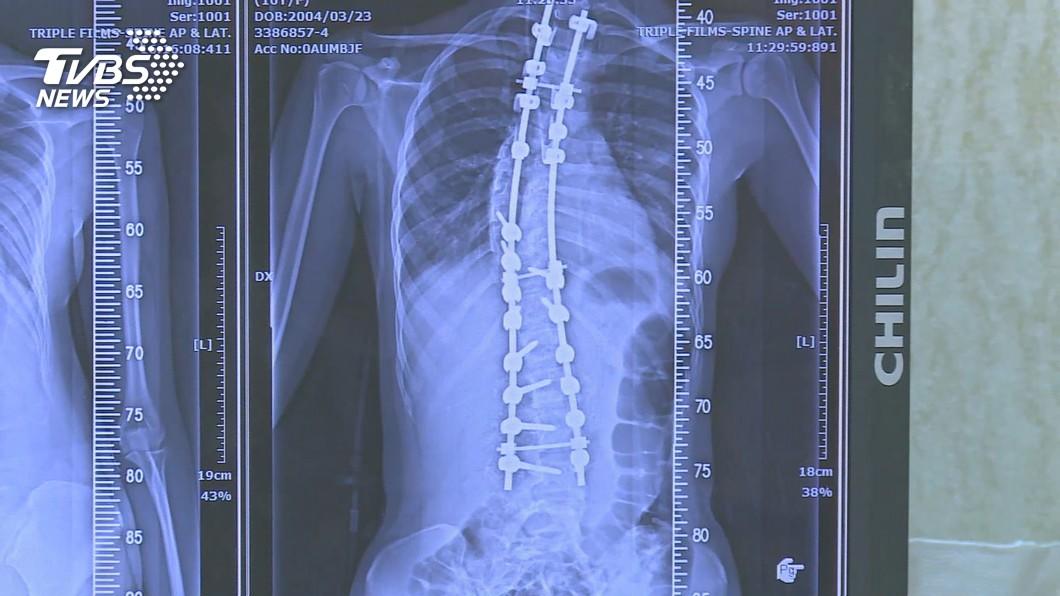

圖片來源:TVBS